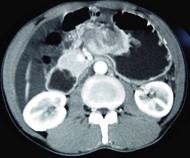

问题 男,65岁,中上腹痛腹胀、消瘦、乏力、纳差,影像检查如图,最可能的诊断是 ( )

选项 A.胃间质瘤 B.萎缩性胃炎 C.肥厚性胃炎 D.胃窦癌 E.胃淋巴瘤

答案 D